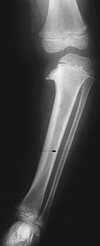

What is this condition? What is the natural hx? What is it associated with?

congenital posteromedial bowing of the tibia. The natural history of this condition is gradual improvement, with the patient being left with a limb-length discrepancy at skeletal maturity. Bowing is associated with a calcaneovalgus deformity of the ipsilateral foot. There is no association with scoliosis and skin lesions. There is no increased risk for bone tumors or neurologic issues with congenital posteromedial bowing of the tibia